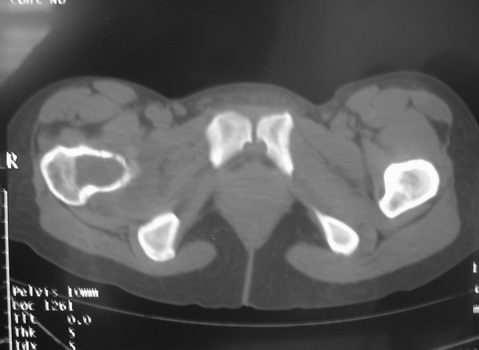

女,31岁,右髋部疼痛半年,加剧两天不能行走

hhcckk发言:右股骨颈囊状骨质破坏,骨皮质变薄,周围硬化边不明显

我与楼主考虑的不太一样,我考虑骨巨的可能性更大

dyqct发言:支持右股骨头、颈骨巨细胞瘤可能性大(跨越骺线).

拾荒者分析:该病例囊肿透亮度较高,骨膨胀轻微,还是要首先考虑骨囊肿。至于与骨细胞瘤的鉴别,影像鉴别困难。我想,发病年龄及临床症状可能是主要参考点。